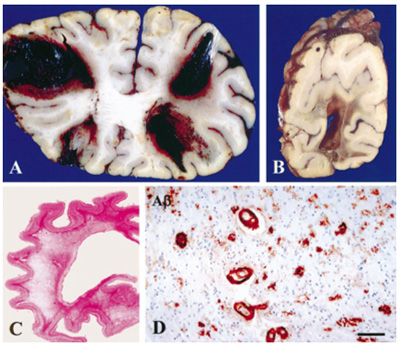

Figure 4. Multiple large hemorrhages in both frontal lobes (A) and occipital lobe (B). Diffuse white matter destruction (C). CAA in many vessels in the cerebral white matter; scale bar 70 µm (D). From [97].

Aβ peptides also involve the vessel walls, as with CAA, with the more soluble Aβ-40 as the major constituent. 85-90% of confirmed AD cases have some degree of CAA [84]. It mainly accumulates in the interstitium between the smooth cells of the tunica media. Small arteries, arterioles and even capillaries in the cerebral cortex and leptomeningeal vessels are affected [85]. Stage 1: vessels are affected in the isocortex, stage 2: involvement of allocortex, and stage 3: basal ganglia, thalamus, pons and medulla oblongata [86]. Others distinguished four patterns [87]: Type 1: APs with or without CAA in the leptomeninges alone; type 2: CAA in both leptomeningeal and deeper penetrating arteries (Fig 1A); type 3: CAA affects both precapillaries and arterioles; type 4 shows Aβ deposition in and around blood vessels. Genetically, type 3 (capillary subtype) is more strongly associated with the APOEε4 allele [87, 88]. Two other types were distinguished: Type 1 affecting capillaries, arterioles and small arteries is associated with APOEε4, whereas type 2 not involving capillaries is more likely associated with APOEε2, its most frequent form [89]. Both severe CAA and AD are associated with APOEε4-positive patients [88]. A more recent staging system is based on the severity of CAA in a single vessel: grade 0: absence of staining, grade 1: a congophilic ring around the otherwise normal-appearing vessel, grade 2: complete replacement of the tunica media by congophilic material, grade 3: involving >50% of vessel circumference, giving a “double-barrel” appearance, and grade 4 or fibrinoid necrosis of the vessel wall with additional amyloid deposits in the surrounding neuropil (“dyshoric changes”) [88]. The parietal and occipital cortices are more vulnerable than the frontal and temporal lobe, and the leptomeningeal vessels more than the parenchymal ones [84]. Aβ deposition shrinks the cerebral blood vessels by about 8% and reduces the energy supply resulting from decrease of blood flow [90]. CAA can cause small infarcts in the cerebral cortex, while severe CAA may lead to lobar hemorrhages in the frontal and occipital lobes and to diffuse white matter lesions (Fig. 4) [91]. Brain hemorrhage does not appear to be directly linked to amyloid burden in patients with CAA-related intracerebral hemorrhage, because amyloid burden was similarly distributed across the brain hemispheres and no interhemispheric difference was observed for Aβ burden nor for MRI markers of small vessel disease [92]. CAA and deep perforating arteriopathy are similar and interact with blood-brain barrier breakdown, endothelial damage, and impaired perivascular Aβ drainage. Both may cause ischemic lesions and intracerebral hemorrhages [93]. Chronic treatment of a mouse model of AD with fungicides produced Aβ fibril formation and impairment of Aβ clearance through neprylisin, suggesting that fungicide residues could be a risk factor for AD via CAA [94]. Although several pathogenic mechanisms, including the disbalance between production and clearance of Aβ creating a self-reinforcing cycle of increased vascular Aβ and further CAA and AD progression, have been shown, they do not explain completely the disease pathogenesis [95]. The intersection between CAA and AD points to a crucial role for improving vascular function in the treatment of AD [96].